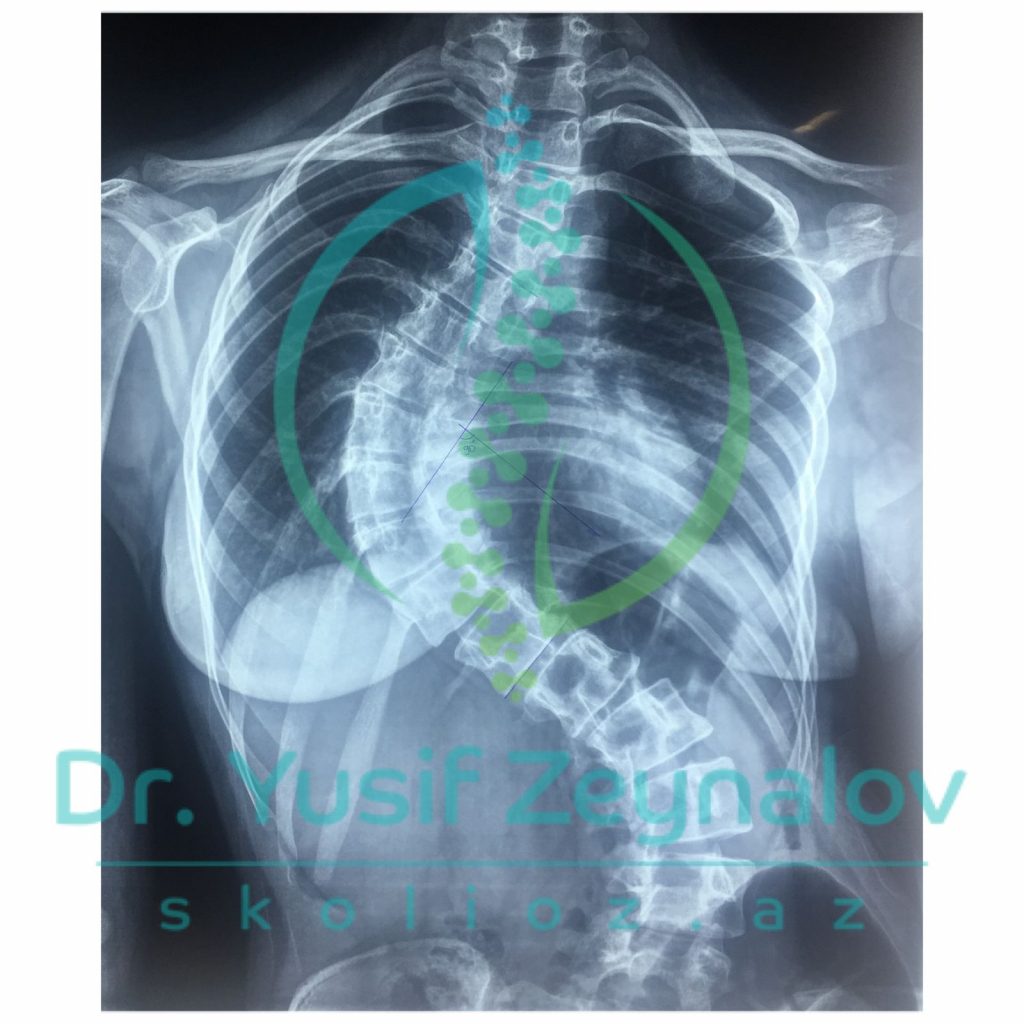

İDİOPATİK SKOLİOZ. COBB BUCAĞI 87°